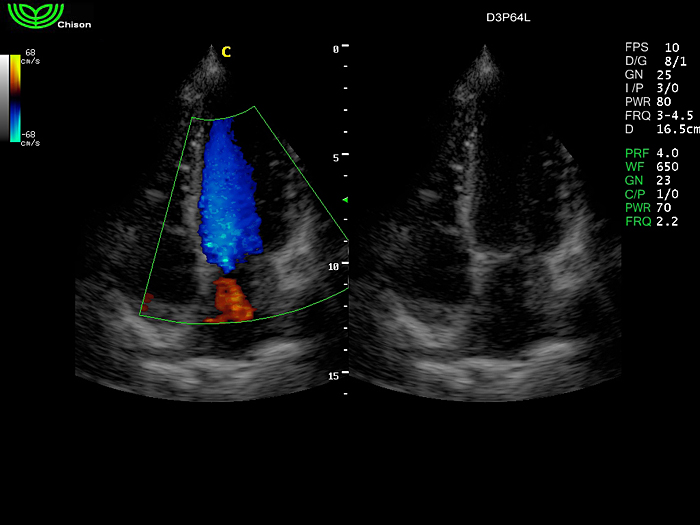

D3P64L 3.0МГц, фазированная решетка.

2.0МГц – 4.4МГц. Применения: кардиология, брюшная полость, акушерство. |